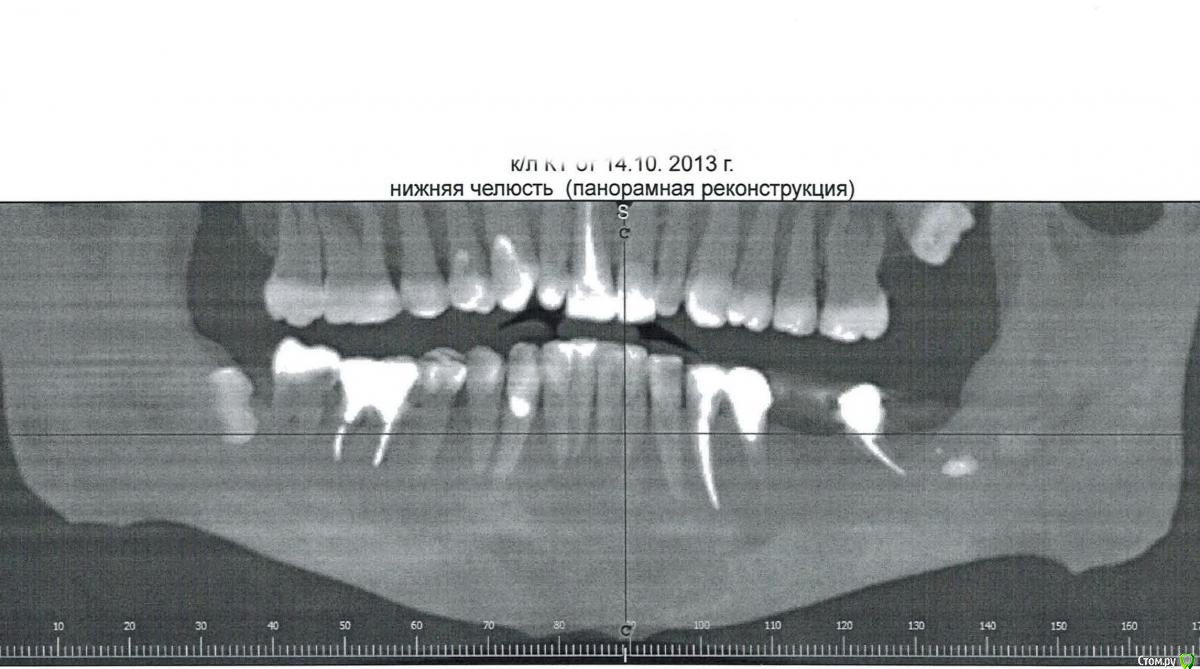

patient2015 Опубликовано 1 октября, 2015 Поделиться Опубликовано 1 октября, 2015 http://s017.radikal.ru/i401/1510/19/68bf52ca58ae.jpg Приветствую! В 2011 при установке культевой вкладки мне пробили корень 46 зуба, я справилась с нагноением промываниями хлоргексидином через свищевой ход, коллапан вскоре тоже растворился, сейчас периодически стали возникать боли при накусывании и опухла десна, примыкающая к 45 с внутренней стороны. Это основной зуб, на котором сейчас ем, т.к. с противоположной стороны мост, который опирается на половинку корня, оставшегося от 37 (в него упиралась ретинированная 8), за 47 ситуация аналогичная, вскоре растворится часть корня. (про одонтому рентгенолог загнул, да и порядок зубов перепутал) Посоветуйте, возможно ли подвинуть 47 к 45 зубу, сроки и цена вопроса? Или только имплантация? Ссылка на комментарий